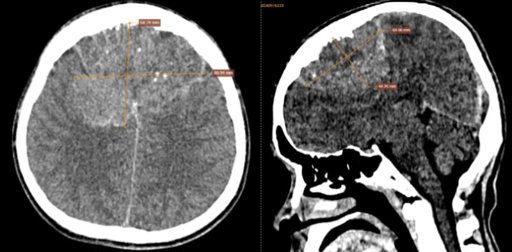

2.8. Triệu chứng khi soi đáy mắt

Khi nghi ngờ bệnh nhân bị viêm thị thần kinh, soi đáy mắt sẽ được thực hiện và giúp xác định được vị trí tổn thương chính xác, cùng với đó là dấu hiệu cương tụ, đĩa thị phù, bờ hơi mờ kèm xuất huyết xung quanh. Nếu viêm thị thần kinh ở dạng hậu nhãn cầu thì thường không phát hiện được tổn thương khi soi đáy mắt.

Soi đáy mắt có thể thấy tổn thương viêm thị thần kinh